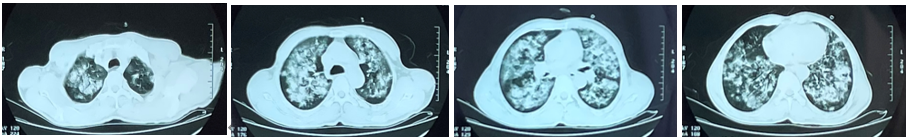

文章配图

入院当天胸片:双肺大片斑片状、絮状致密影,边界不清

广州市第一人民医院呼吸与危重症医学科主任医师梁志科介绍,患者的情况比较棘手,在呼吸机支持下氧合不佳,氧合指数仅为167mmHg(正常>300);纤支镜下见中量黄脓痰,气道黏膜充血水肿、糜烂;血常规白细胞为20.81x10^9/L(正常范围:4-10x10^9/L),炎症因子升高。“我们诊断患者患有重症肺炎急性呼吸窘迫综合征(ARDS,中度),同时出现急性肾功能不全、急性肝功能不全、心肌损伤、弥散性血管内凝血(DIC)、重度溶血性贫血、下肢深静脉血栓形成、多腔膜积液、心脏瓣膜病等情况,各项指标都不容乐观。”